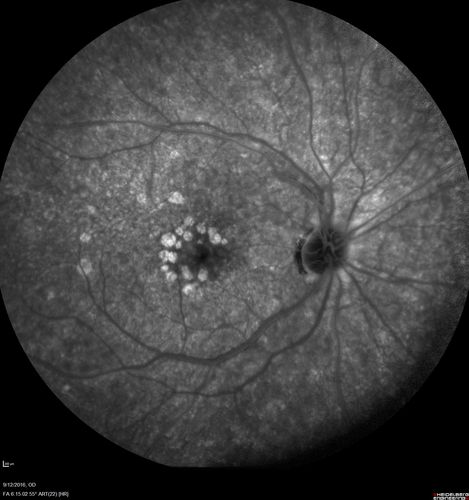

Syphilitic Chorioretinitis

Severe outer retinal atrophy and RPE non-geographic atrophy from syphilis.  Vision improved from 20/63 to 20/32 with therapy.  Images look a lot like DUSN.  Patient had several surgeries (vitrectomy for floaters, vitrectomy for macular pucker, Avastin injections and macular laser for edema) prior by other retina specialists prior to being correctly diagnosed and treated.